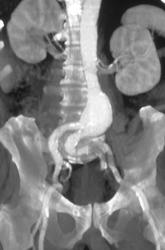

Diagnosis

Endovascular Stent